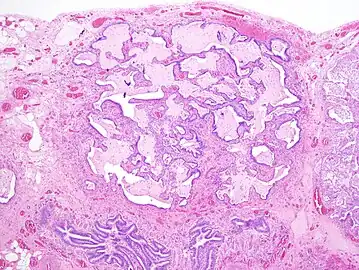

The histologic hallmarks of UIP, as seen in lung tissue under a microscope by a pathologist, are interstitial fibrosis in a "patchwork pattern", honeycomb change and fibroblast foci (see images below).[6] [7]

Appearance of honeycomb change in a surgical lung biopsy at low magnification. The dilated spaces seen here are filled with mucin. Hematoxylin-eosin stain, low magnification. -